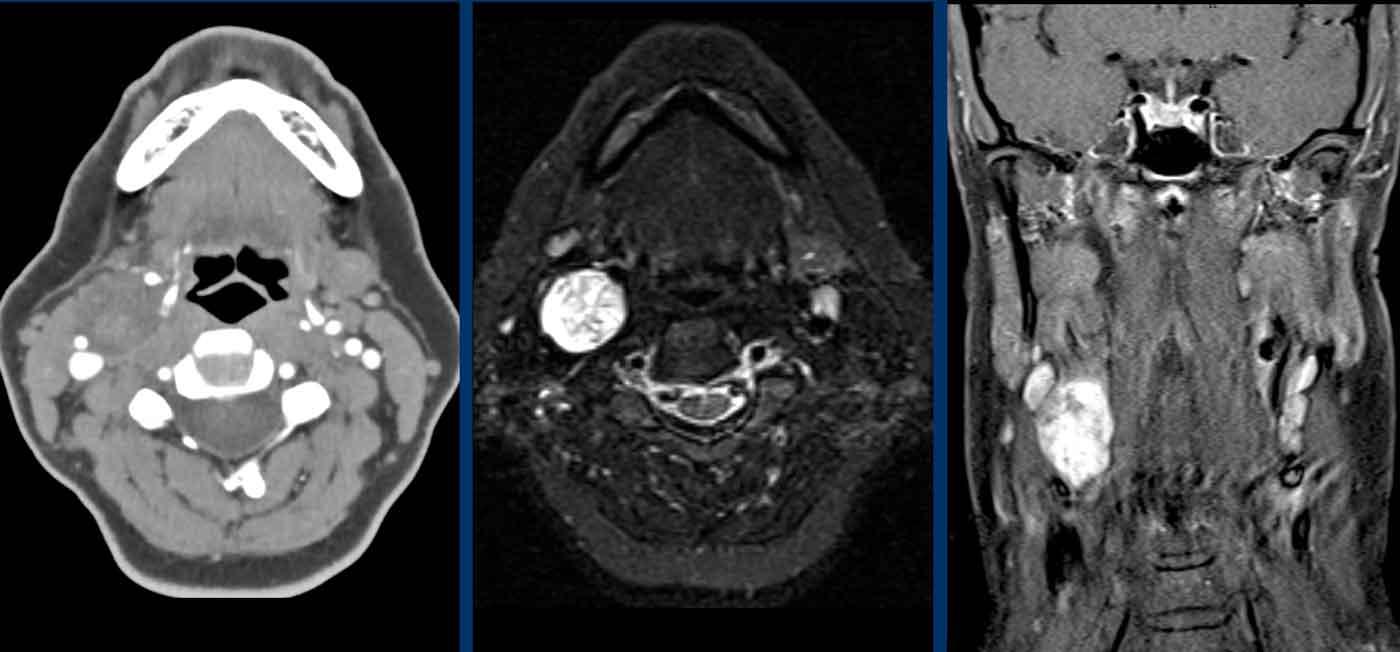

Ca lâm sàng

Hình ảnh của một người đàn ông 45 tuổi với khối u cổ không có triệu chứng và hội chứng Horner được phát hiện khi khám lâm sàng.

Images

- CTA cổ cho thấy một khối u trong khoang cảnh bên phải.

Không có tăng ngấm thuốc động mạch sớm thực sự.

Động mạch cảnh trong bị đẩy lệch về phía trước-trong và tĩnh mạch cảnh bị đẩy lệch về phía sau-ngoài. - T2WI cho thấy một tổn thương tăng tín hiệu.

Ở phía bên trái có một số hạch bạch huyết, không có hạch nào phì đại bệnh lý. - Coronal T1W-image shows late contrast enhancement.

Kết luận

Đây là u bao thần kinh (schwannoma).

U cận hạch (paraganglioma) sẽ cho thấy hình ảnh ngấm thuốc sớm trên CT.